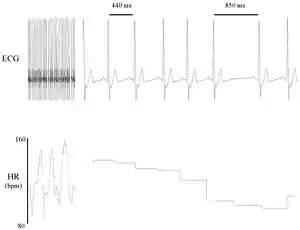

La variabilidad de la frecuencia cardíaca (VFC) es el fenómeno fisiológico de la variación en el intervalo de tiempo entre cada latido cardíaco. Se mide por la variación en el intervalo de latido a latido.

Otros términos utilizados incluyen: "variabilidad de la duración del ciclo", "variabilidad de RR" (donde R es un punto que corresponde al pico del complejo QRS de la onda de ECG ; y RR es el intervalo entre Rs sucesivas), y "variabilidad del período del corazón" .

Los variantes utilizados para detectar latidos incluyen: ECG, presión arterial, balistocardiogramas.[1][2] y la señal de onda de pulso derivada de un fotopletismógrafo (FPG). El ECG se considera superior porque proporciona una forma de onda clara, lo que facilita la exclusión de los latidos del corazón que no se originan en el nodo sinoauricular . El término "NN" se usa en lugar de RR para enfatizar el hecho de que los tiempos procesados son tiempos "normales".